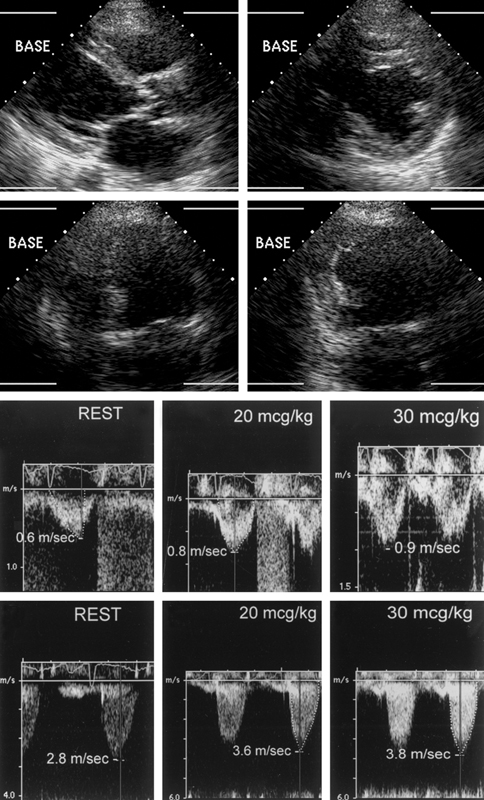

فحوصات تشخيصية لبعض امراض القلب والشرايين التاجية